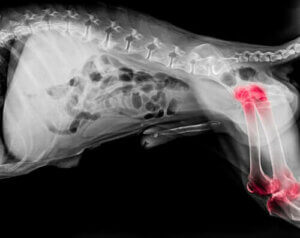

Experter tror att uppskattningsvis en av fem hundar drabbas av artrit. Denna ledsjukdom kan dyka upp närsomhelst, men den är vanligare hos äldre hundar.

Brett talat är artrit en degenerativ sjukdom som orsakar inflammation i både armbågs- och axelleder. Vanliga symptom på artrit inkluderar: